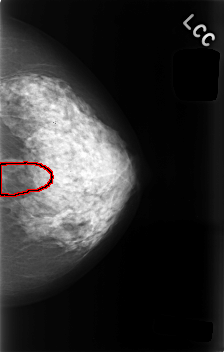

C_0495_1.LEFT_CC

LEFT_CC LINES 4576 PIXELS_PER_LINE 2912 BITS_PER_PIXEL 12 RESOLUTION 50 OVERLAY

FILE: C_0495_1.LEFT_CC.OVERLAY

TOTAL_ABNORMALITIES 1

ABNORMALITY 1

LESION_TYPE CALCIFICATION TYPE AMORPHOUS DISTRIBUTION SEGMENTAL

ASSESSMENT 4

SUBTLETY 2

PATHOLOGY BENIGN

TOTAL_OUTLINES 1

BOUNDARY